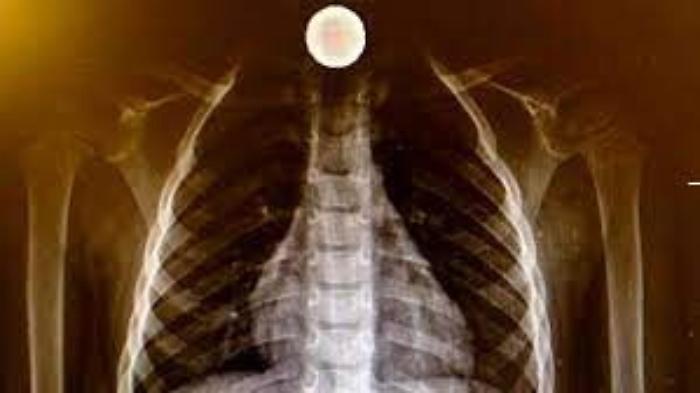

A quel punto i due medici hanno deciso di sottoporre il bimbo a una radiografia del torace dalla quale è emerso che la moneta era ferma nella parte alta dell’esofago. Vista la necessità di sottoporre il piccolo a endoscopia pediatrica è stato disposto il trasferimento all’ospedale dei Bambini Di Cristina di Palermo dove, così come previsto dai protocolli per il trattamento dei pazienti, potrà essere eseguita la procedura in completa sicurezza. Il trasferimento è avvenuto mediante l’elisoccorso messo a disposizione dalla sala operativa del 118 di Caltanissetta.